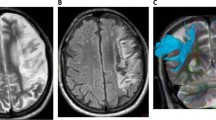

Lesion Mapping

We constructed a lesion overlap image for all aphasic patients. A radiologist (Y.L.) manually traced the outline of the lesion on individual 3D T1 images using MRIcron (http://www.mccauslandcenter.sc.edu/mricro/mricron/), thereby creating a lesion mask for each patient. After the spatial normalization process, the union of all individual lesion mask was used to construct a group lesion mask for the patients (Fig. 1).